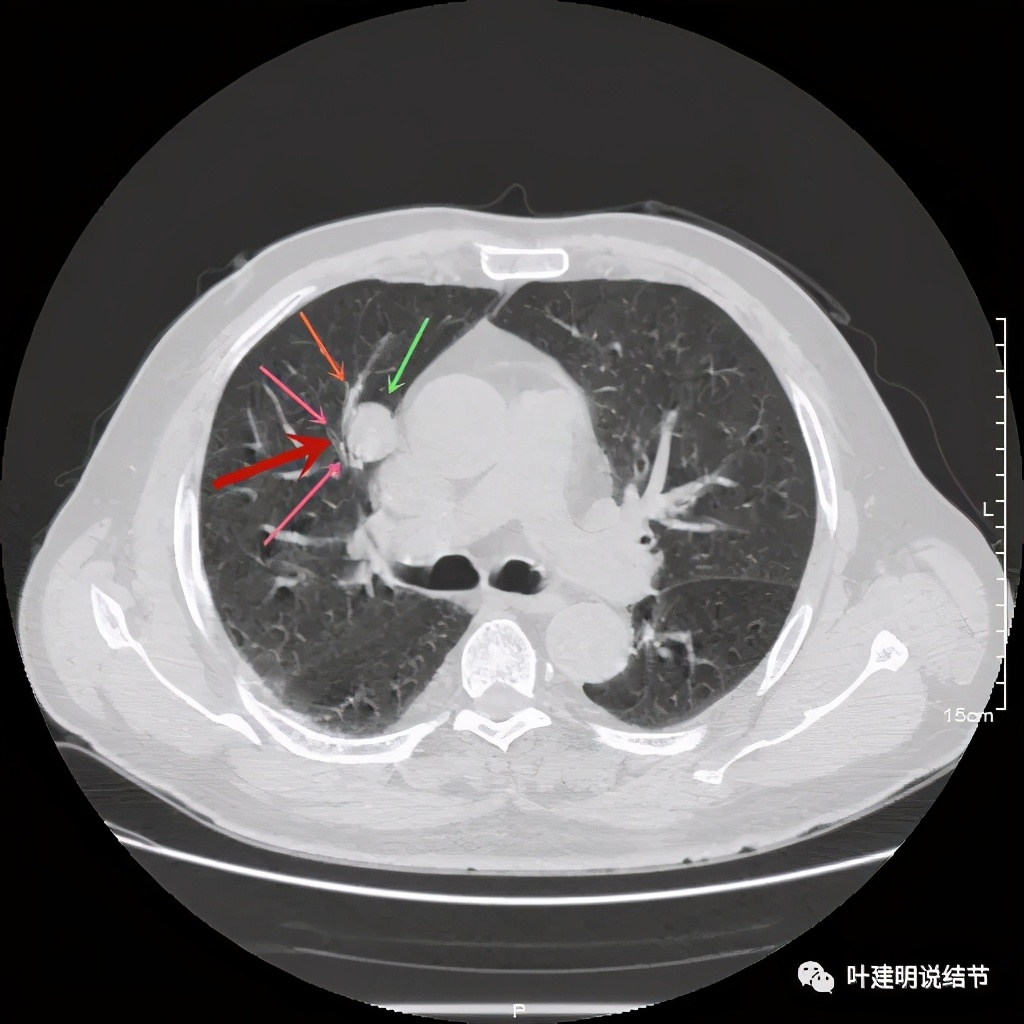

上图示病灶密度不均,但边缘过于光滑(绿色);支气管似有截断(粉色);局部有点状钙化(蓝色)

上图也示病灶密度不均,但边缘过于光滑(绿色);支气管似有截断(粉色);局部有点状钙化(蓝色)

病灶在上图层面似见支气管也是贴壁的。那么增强后又是如何呢?